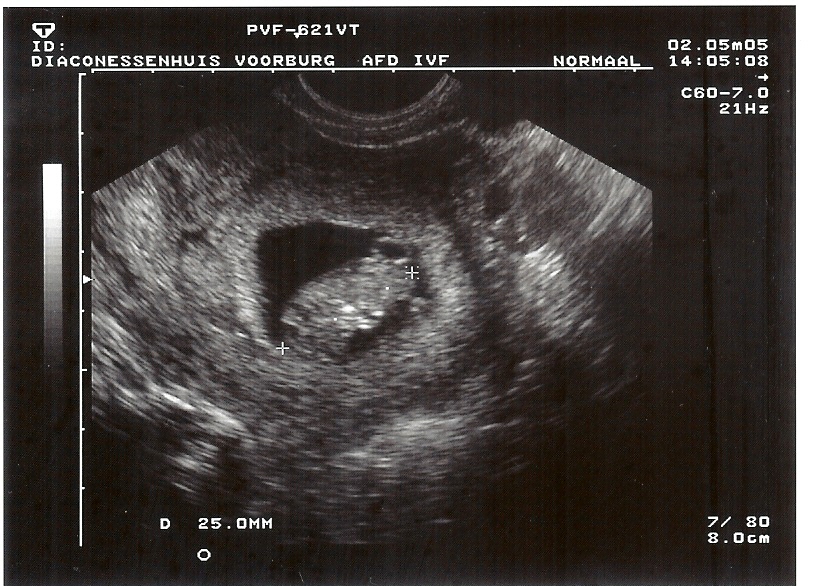

2-5-2005 Charmain 9 weken, 4 dagen, 25mm